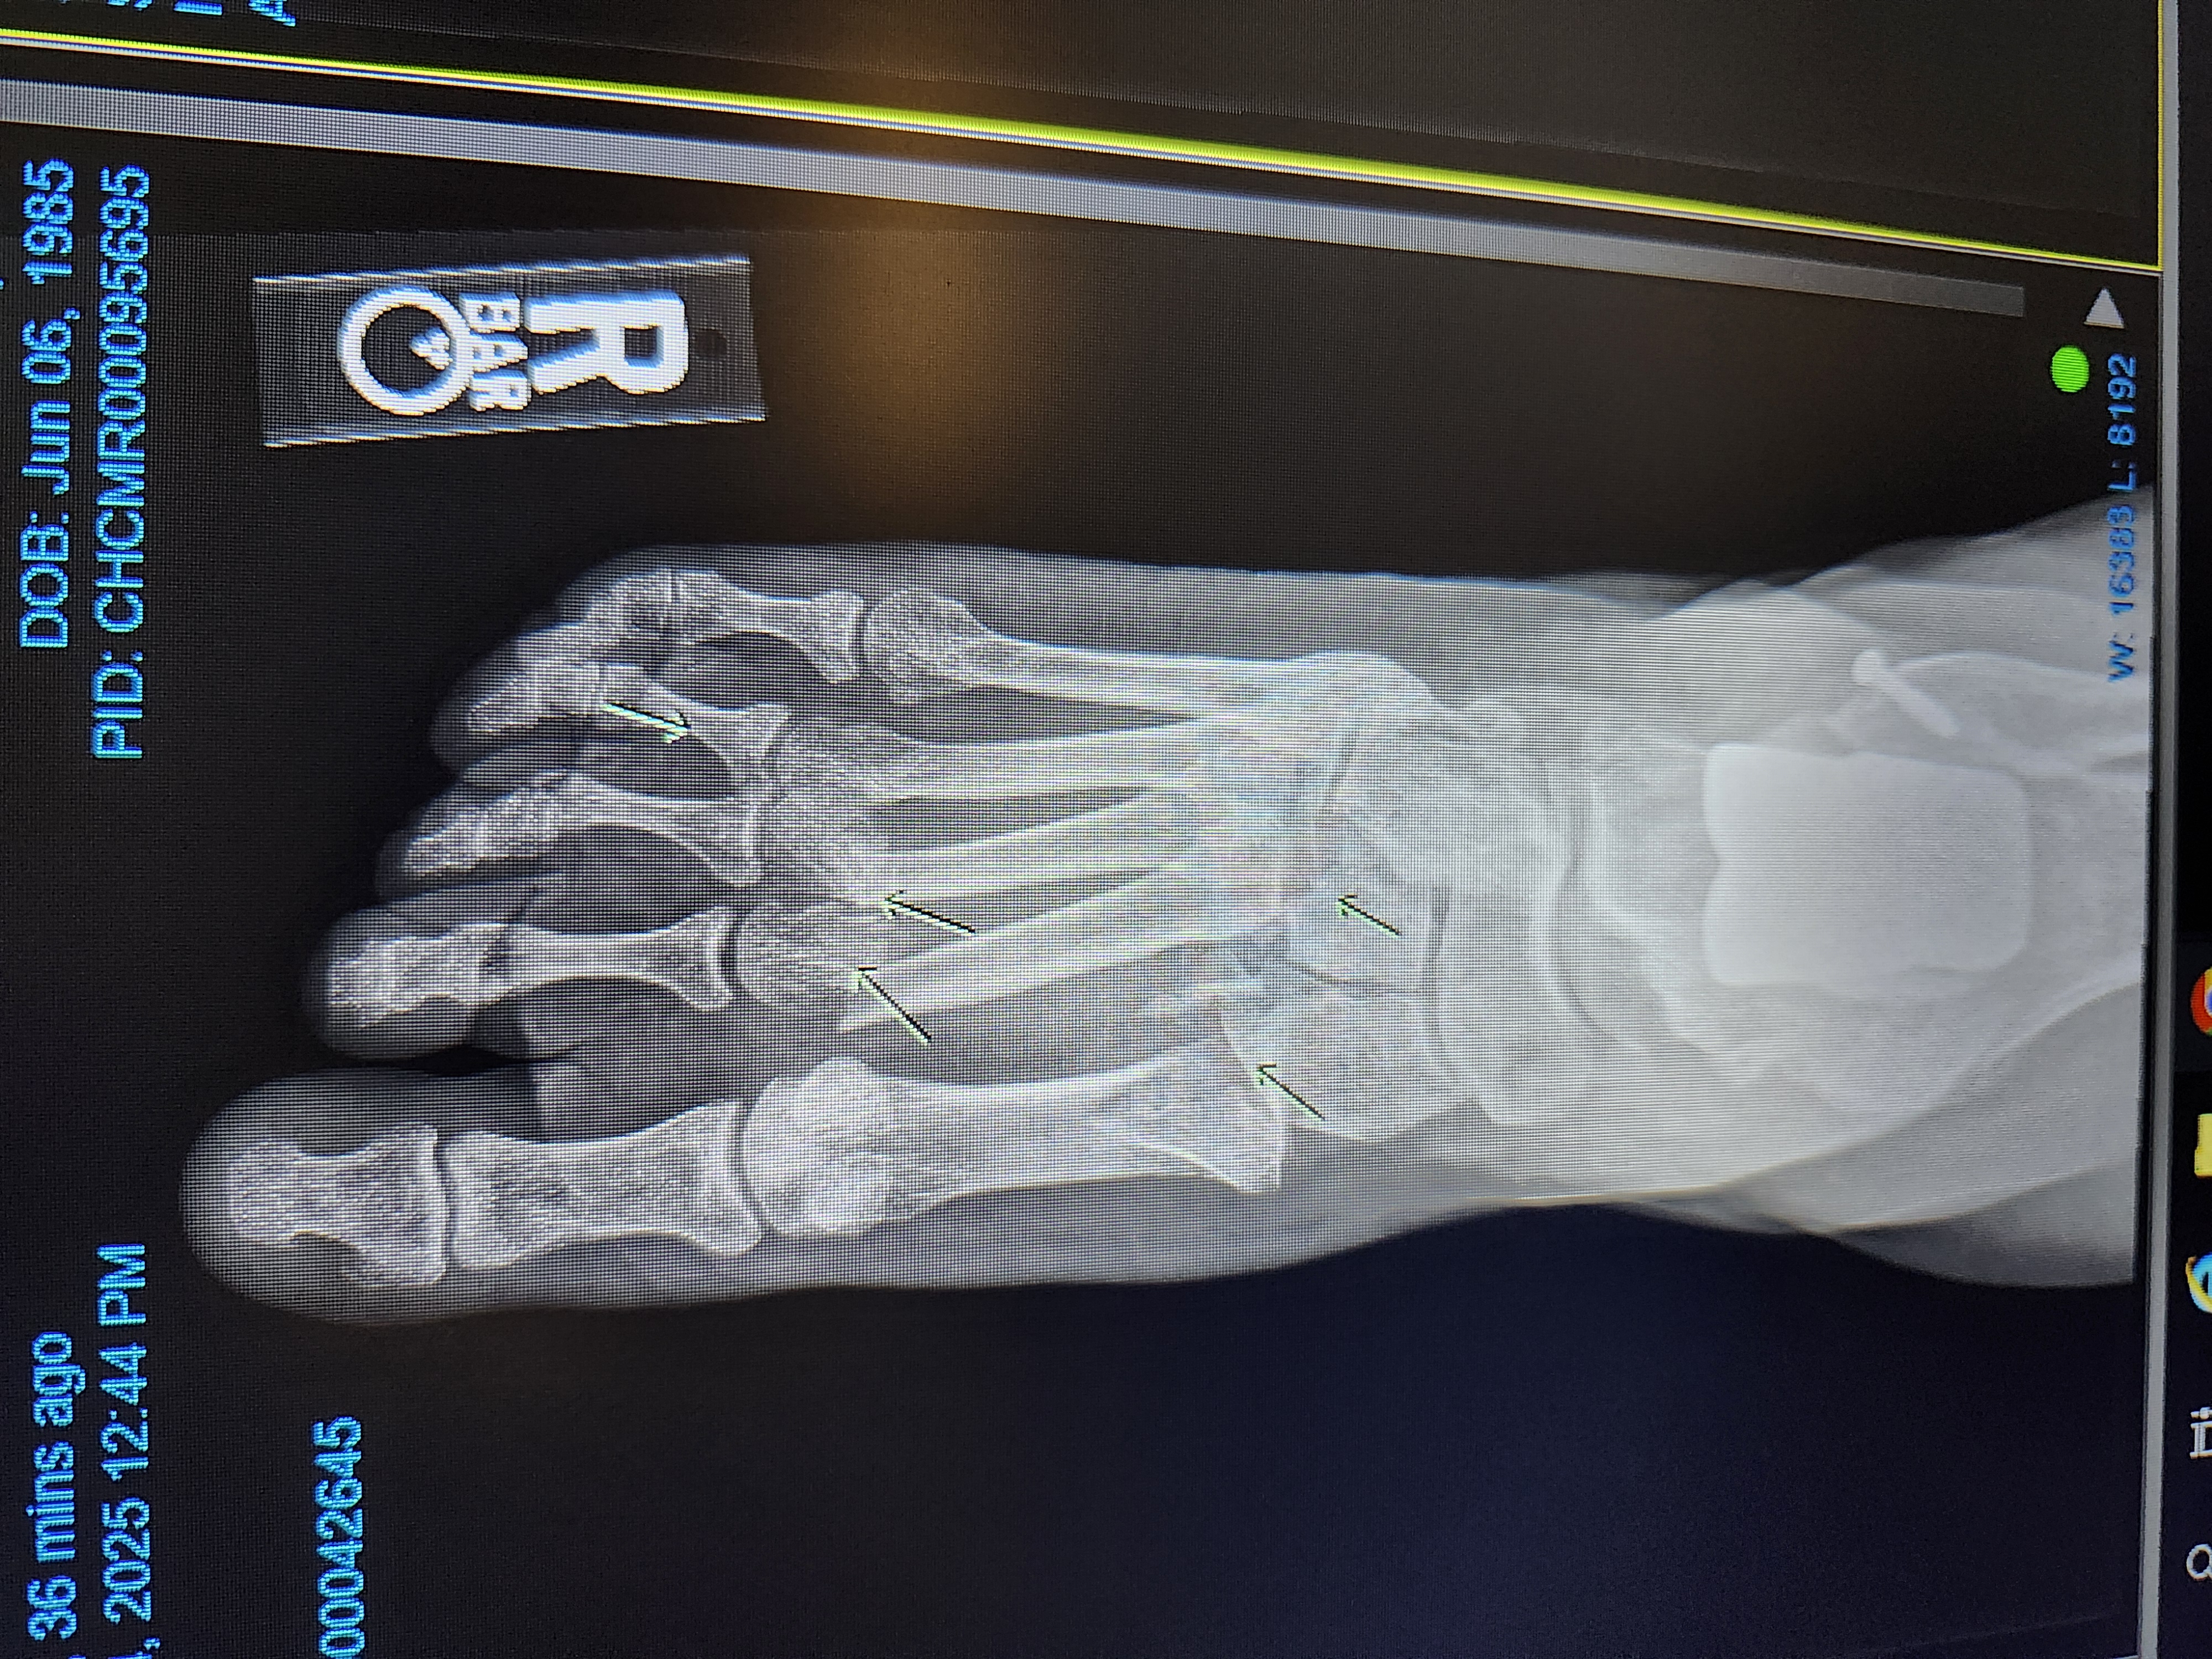

A few weeks ago, my mom had a terrible fall that changed everything. She broke nearly every bone in her right foot — the same foot where she already had an ankle replacement — and also fractured her left leg. On top of that, she suffered a head injury. The swelling was so bad that doctors couldn’t do surgery right away, and even after sedation to reset the bones, she’s still in intense pain. She was sent home but fell again trying to get up our steps and is now back at the University of Iowa Hospitals for care.